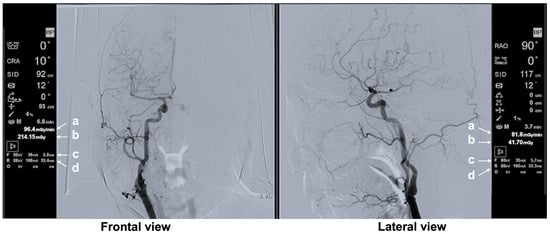

3.3.3. Typical Scene 3 (Case 3)

3.3.4. Typical Scene 4 (Case 3)

| Typical Scene No. | Case No. | DSA Site | X-Ray Projection | FPD Size (inch) | SID (cm) | Ka,r (mGy) | Table Height (cm) | Cervical Unprotected Dose Rate (mSv/h) | Chest Unprotected Dose Rate (mSv/h) | Cervical/Chest Unprotected Dose Rate Ratio |

|---|---|---|---|---|---|---|---|---|---|---|

| 3 | 3 | Lt C-CAG | Frontal—LAO 0°, Cranial 1° | 12 | 90 | 80.06 | 93 | 0.48 | 1.65 | 0.29 |

| Lateral—RAO 90°, Cranial 0° | 12 | 111 | 100.1 | |||||||

| 4 | 3 | Lt SAG | Frontal—LAO 0°, Cranial 0° | 12 | 91 | 93.2 | 94 | 1.01 | 3.20 | 0.32 |

| Lateral—RAO 90°, Cranial 0° | 12 | 112 | 107 | |||||||